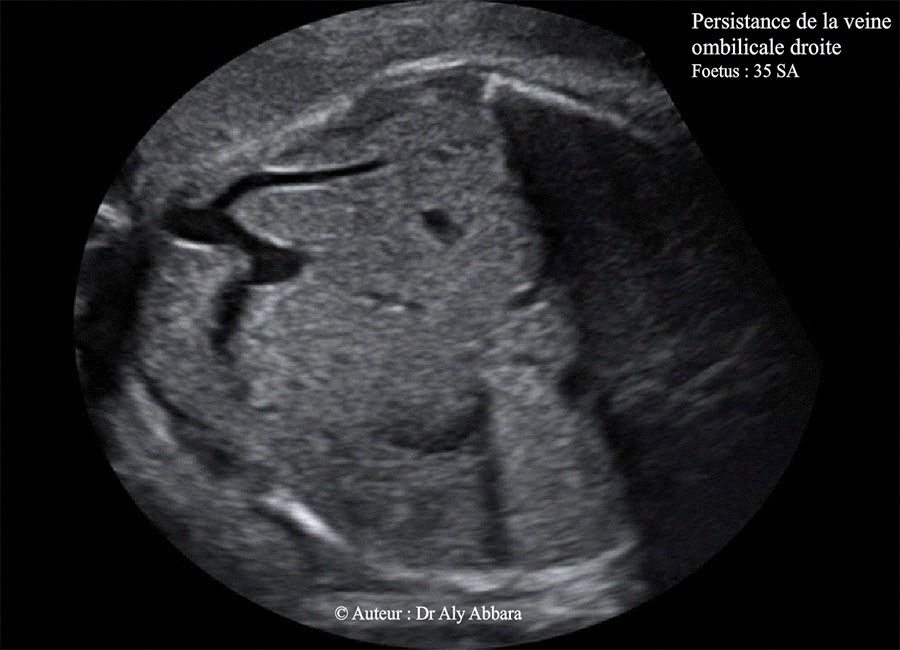

Veine ombilicale droite persistante - 35 SA - Images A

Images échographiques montrant une veine ombilicale à deux branches droites, la première est extra-hépatique et la deuxième est intrahépatique ; puis un trajet inhabituel de la branche gauche de de la veine ombilicale qui se dirige vers la région anatomique à gauche de l'estomac.

Le canal veineux naît de la veine ombilicale comme une branche intermédiaire qui n'atteint pas la veine cave inférieure sur aucune coupe réalisée lors de l'étude Doppler de cette anomalie.

(Variante de la veine ombilicale droite persistante ?).

Foetus de 35 SA ; aucune anomalie morphologique associée ; foetus eutrophe à la naissance.

b- Veine ombilicale à deux branches droites, extrahépatique et intrahépatique

(le cas présenté dans cette page)